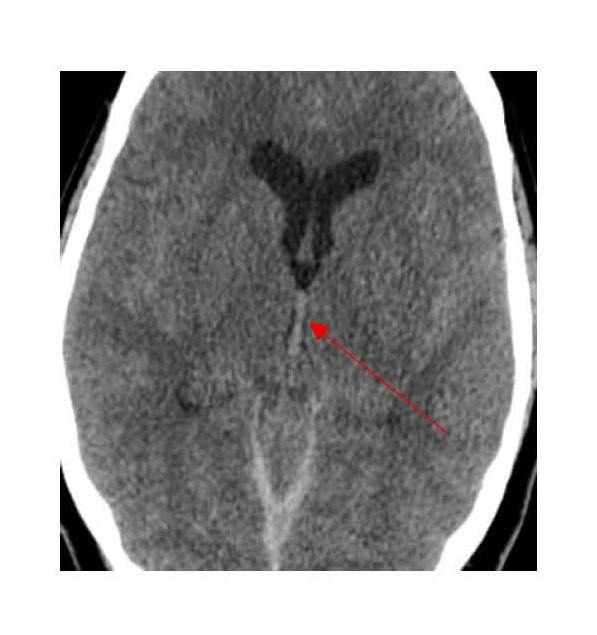

On examination in the emergency department, no external signs of trauma were observed. She was alert but lethargic, and was able to follow commands with no focal neurological deficits. Her initial NIH Stroke Scale score was 0, and her Glasgow coma scale score was 15. A heart examination demonstrated regular rate and rhythm, and a chest examination revealed bilateral rhonchi. Her laboratory data yielded notable findings for glucose (239 mg/dL), Na (137 mEq/L ), K (3.3 mEq/L ), CO2 (17 mEq/L ), anion gap (21), BUN (14 mg/dL), Creatinine (0.9 mg/dL), Troponin (418 ng/L; reference normal range ≤14 ng/L), hemoglobin (13.9 g/dL), hematocrit (43.0%), platelets (360 K/uL), WBC count (17.9 K/uL with neutrophils 44.8%, Lymphocytes 45.3%, monocytes 6%, Eosinophils 2.6%, basophils 0.6% and immature neutrophils 0.7%). Arterial blood gases: pH of 7.25, PCO2 of 51 mm Hg, PO2 of 90 mm Hg, and blood carbon monoxide of 2.1% (reference range 0-5%). A chest X-ray showed bilateral diffuse patchy infiltrates predominantly in the mid to lower lung zones. A CT scan of the head without contrast revealed multicompartment hemorrhages, including diffuse SAHs predominantly within the basal cisterns including the bilateral perimesencephalic, prepontine, quadrigeminal, and suprasellar cisterns, as well as small SAH foci within the bilateral sylvian cisterns, which were associated with fourth ventricle intraventricular hemorrhage and small bilateral subdural hematomas along the tentorium (Figure 2).

Figure 2. Head CT showing subarachnoid hemorrhage and small tentorial subdural hematomas.